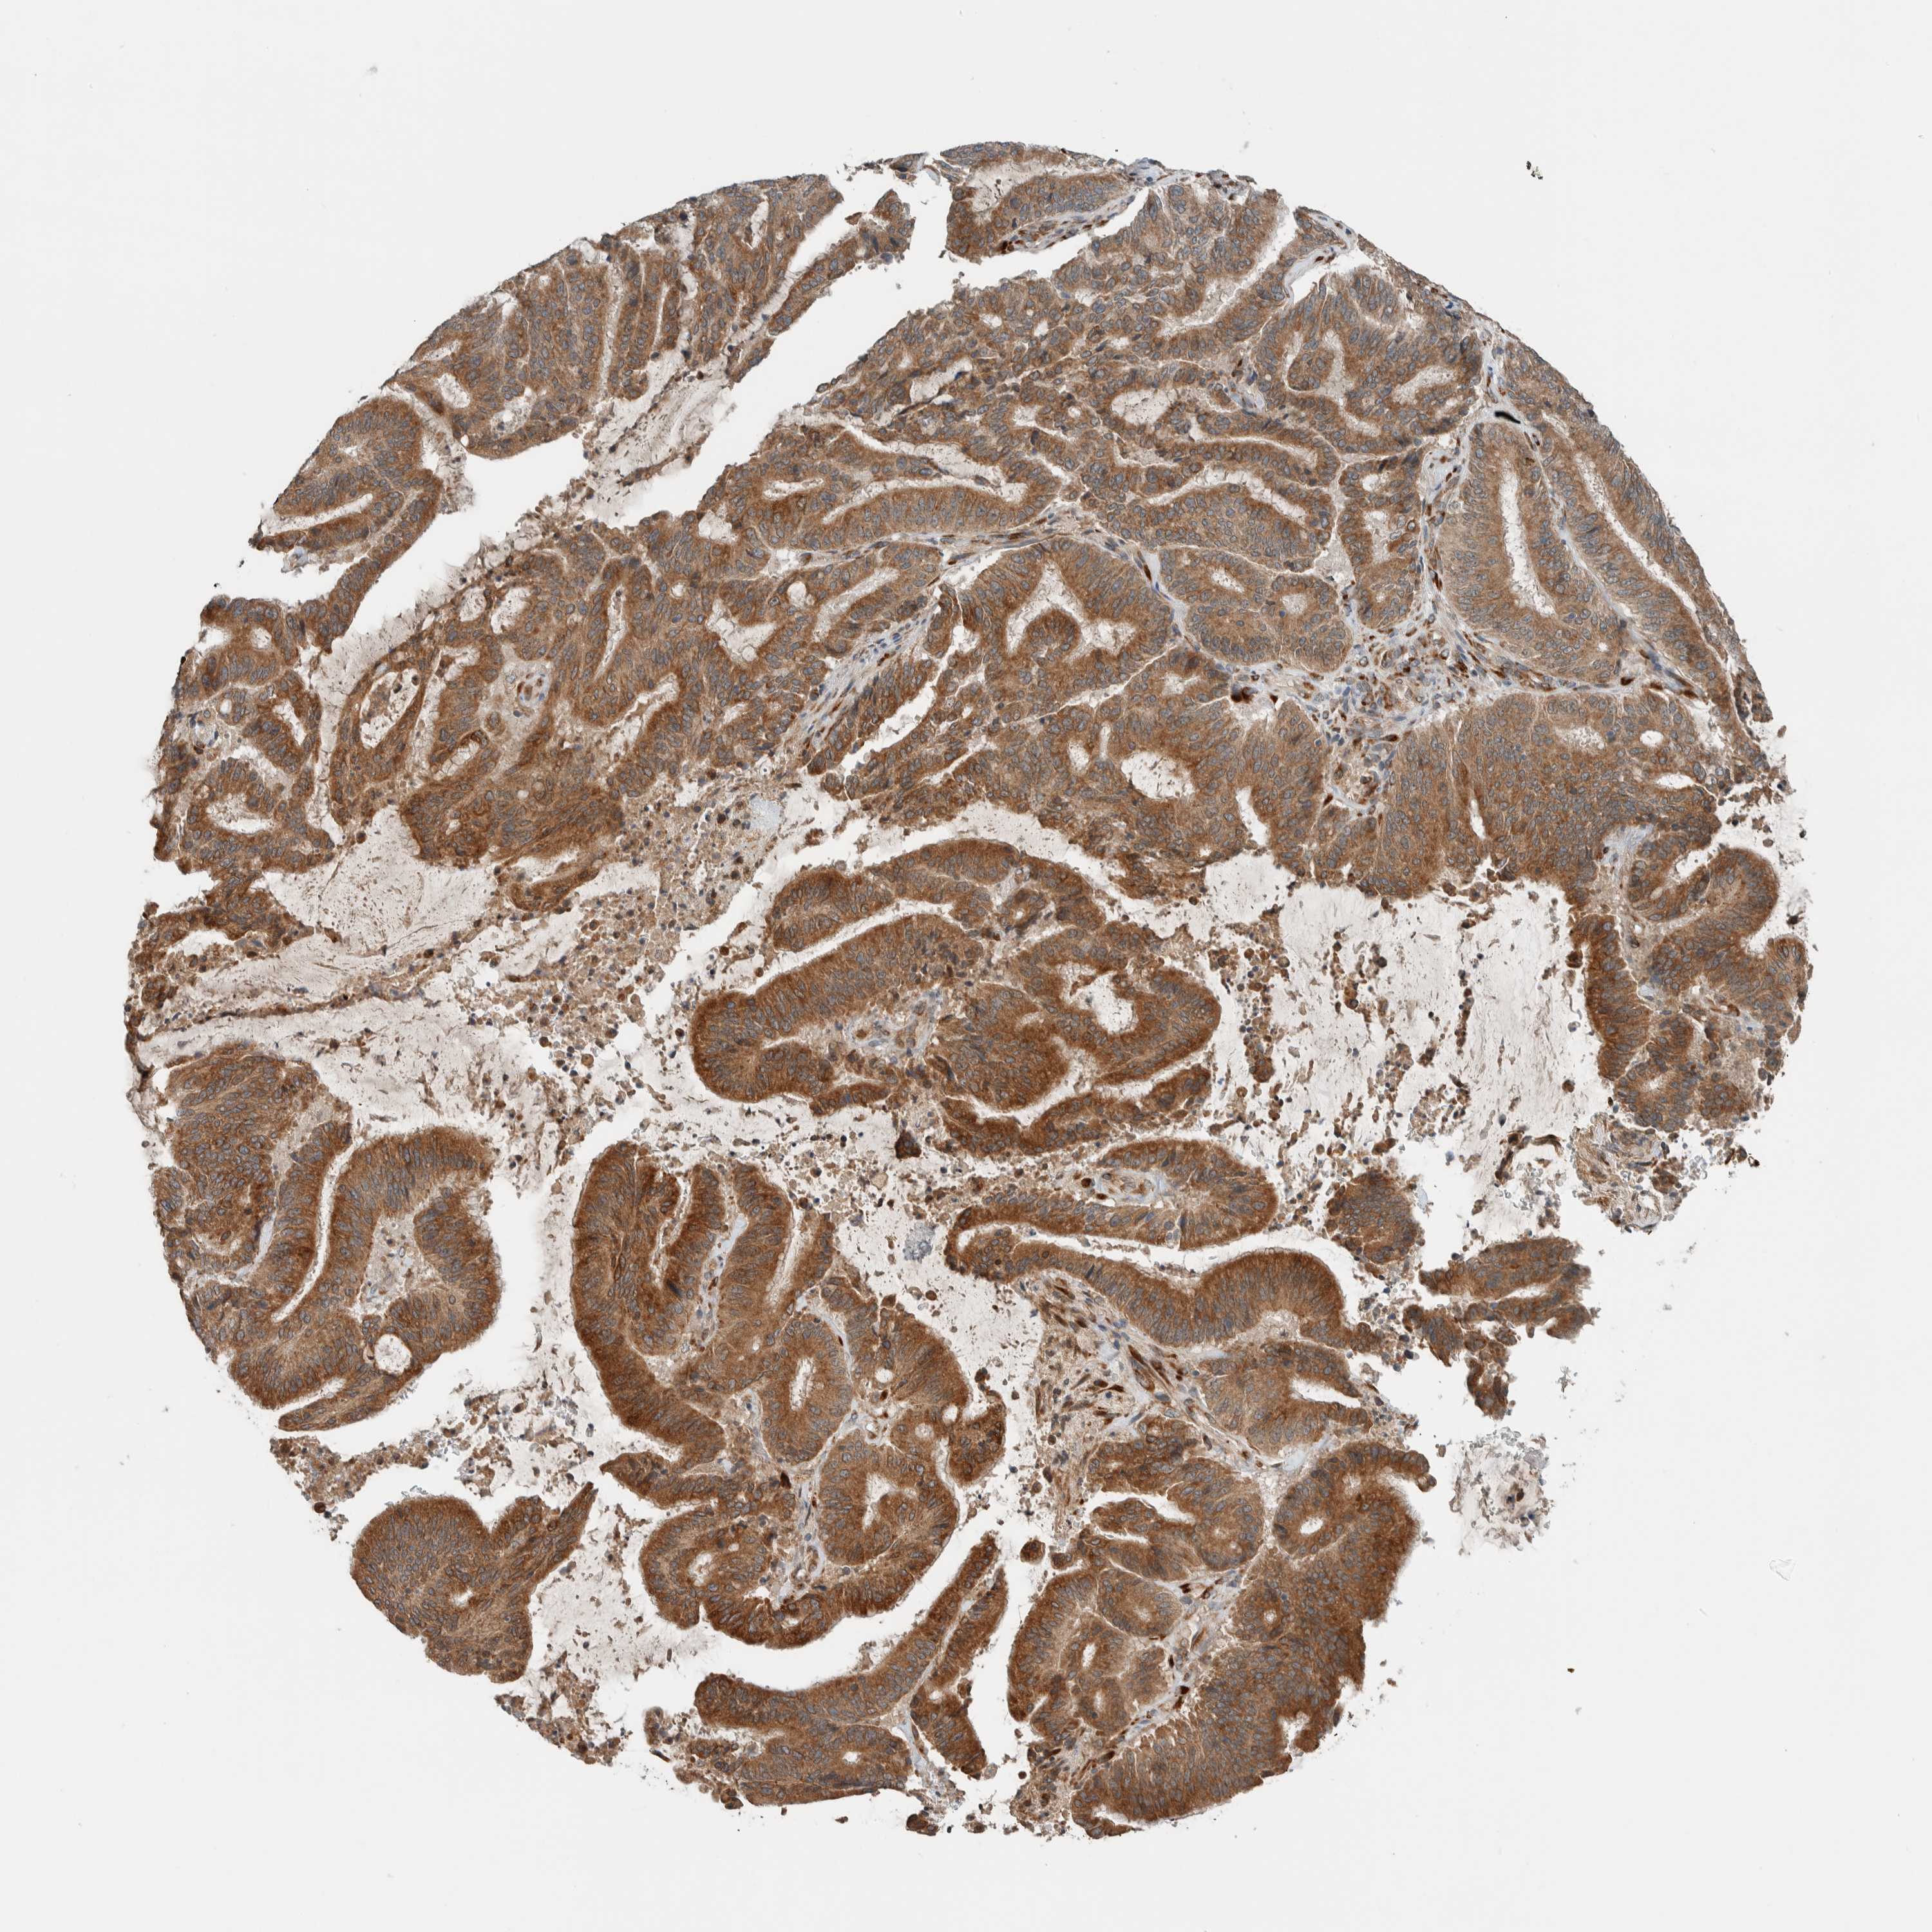

LIVER CANCER - Protein expressioni

A mouse-over function shows sample information and annotation data. Click on an image to view it in a full screen mode. Samples can be filtered based on level of antibody staining by selecting one or several of the following categories: high, medium, low and not detected. The assay and annotation is described here.

Note that samples used for immunohistochemistry by the Human Protein Atlas do not correspond to samples in the TCGA dataset.

Antibody stainingi

Antibody staining in the annotated cell types in the current human tissue is reported as not detected, low, medium, or high, based on conventional immunohistochemistry profiling in selected tissues. This score is based on the combination of the staining intensity and fraction of stained cells.

Each image is clickable and will lead to virtual microscopy that enables deeper exploration of all samples and also displays staining intensity scores, fraction scores and subcellular localization as well as patient and tissue information for each sample.

Antibody HPA023559

Antibody HPA023564

Antibody HPA044971

Antibody CAB031916

Cholangiocarcinoma

Carcinoma, Hepatocellular, NOS